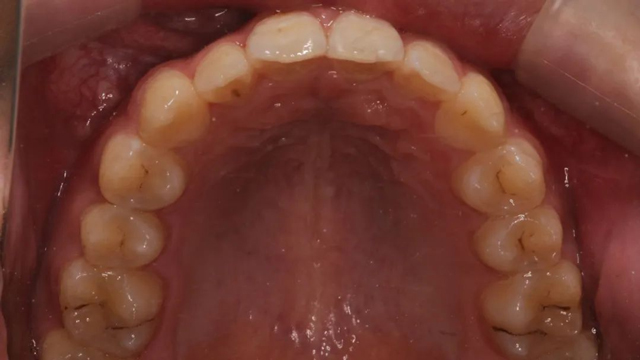

2024年9月(矫正结束后口内照)

据介绍,这个病例最复杂之处就是阻生牙的牵引。从矫正开始,医生以目标为向导制定矫正步骤,利用隐形牙套的优势,以及牙根可视化引导牙齿走向目标位,过程中密切关注阻生尖牙的方向及萌出情况,治疗过程中不断根据具体情况进行调整牵引方向和力的大小,牵引治疗几乎贯穿了矫正的全过程。

“由于这是一颗尖牙,外形比较圆润,并且是口内牙根最长的牙齿,矫治器力不太容易表达,所以移动时会更难一些,从牙齿出龈到建颌,每一步都离不开我们精心的设计。”

该病例的治疗周期长达三年,跨替牙期和年轻恒牙期。治疗结束时,小患者收获了一口整齐美观的牙齿,也从满脸稚气的孩童长成了青葱少年。